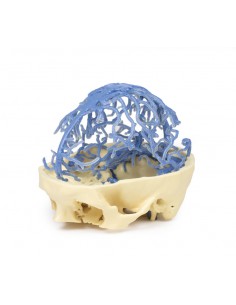

Anatomía 3D 1.0